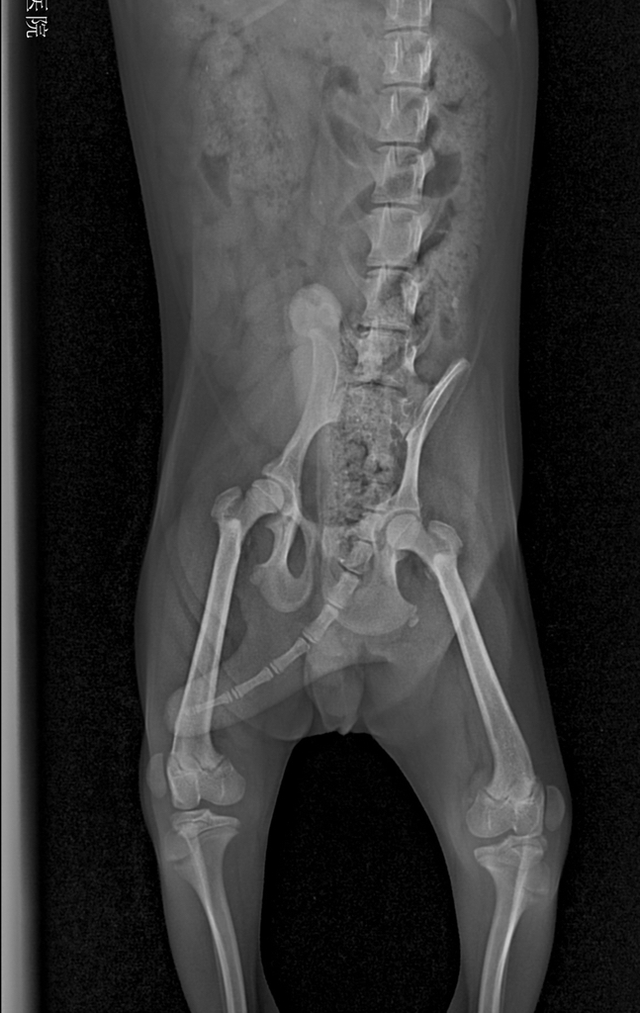

根据主人的症状描述,没有任何外伤和刺激狗狗突然后腿不敢着地,然后跑起来会自行恢复,配合宠物医生的髌骨部位触诊,以及照射x光后,即可确诊。

泰迪狗髌骨脱位怎么办,泰迪狗髌骨脱位吃什么药好(没达到这些标准是不需要手术治疗的)